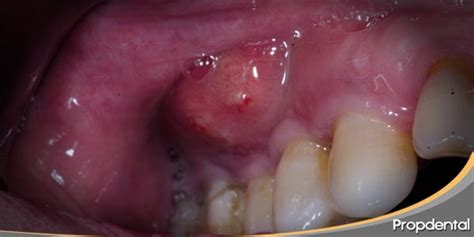

Un flemón, o absceso dental, es una acumulación de pus en la boca, generalmente junto a un diente o en la encía, causada por una infección. Presentar un flemón o un absceso, en la mayoría de los casos, es una experiencia muy dolorosa y desagradable. Te miras al espejo, notas una inflamación en la encía y ves una bolita blanquecina, como una especie de grano, que al presionarla suelta pus. El pus es una mezcla de células muertas, bacterias y fluidos corporales que se forma como respuesta del organismo a una infección. Cuando hay pus, hay infección.

Resulta evidente que la sintomatología más clara siempre pasa por un cuadro de dolor, inflamación de la encía y un acúmulo de pus. Es frecuente encontrar que el dolor no se manifiesta únicamente en el flemón, sino que también ataca a zonas como la mandíbula o el oído. A menudo en una fase inicial puede que no haya presencia de dolor, pero con el avance del proceso infeccioso este aparecerá. Presentar una cara hinchada por el flemón suele ser el signo más llamativo de esta afección. La presencia de pus no debe pasarse por alto, ya que puede tener consecuencias serias si no se trata a tiempo.

Un absceso es una infección bucodental, una enfermedad de las encías, que se manifiesta por la aparición de pequeñas bolsas de pus en diversas zonas del diente. Suelen ser muy molestos y, en ocasiones, pueden causar un dolor de dientes insoportable. Existen tres tipos de abscesos dentales: los abscesos endodónticos, que suelen aparecer en la punta de la raíz de un diente como resultado de la presencia de caries o por un traumatismo (por ello, es importante el cuidado con la placa bacteriana); los abscesos periodontales, que surgen en las encías como causa de alguna enfermedad o enfermedad periodontal; los abscesos combinados, que se presentan cuando el absceso afecta a la raíz dental y a la encía en un punto de intersección entre ambos y los abscesos periapicales, basados en una concentración de pus en la punta del diente causada por una infección. Estos últimos, en la mayoría de los casos, tienen su origen en caries dentales no tratadas.

Por otro lado, en los abscesos periodontales, puede verse el forúnculo infectado en las encías. Se nota además una cierta inflamación en la zona que lo rodea de las encías. A veces, se tiene mal sabor de boca y halitosis.